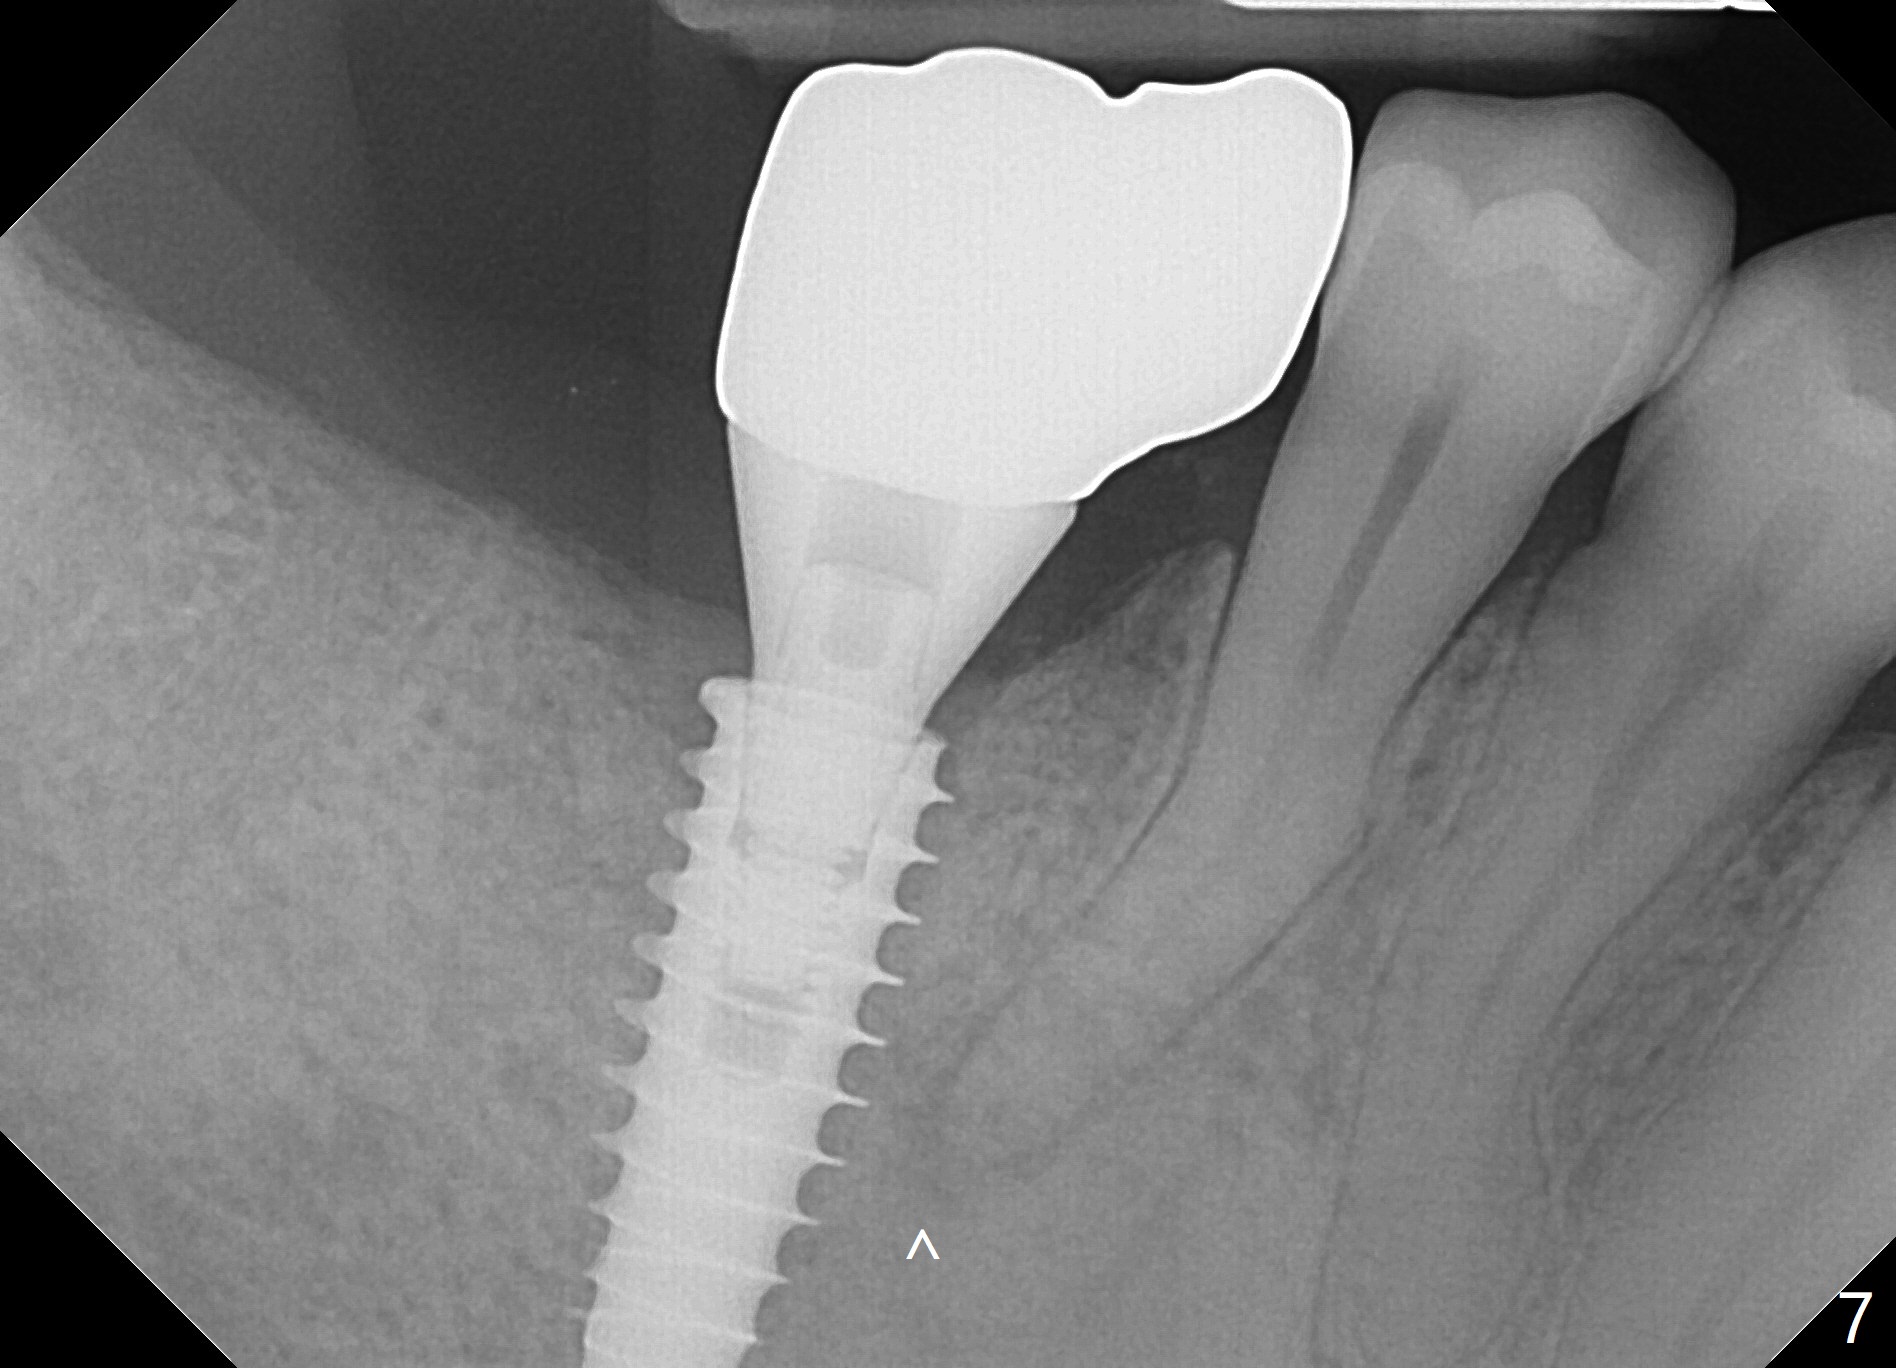

Bone graft seems to sink down and becomes denser 3 months postop (Fig.6 arrow). The bone continues being denser 5 months postop (Fig.7). There is periapical radiolucency of the tooth #29 (^). RCT is done (Fig.8). The pain persists 2 weeks postop (Fig.9,10). There is no missing canal (Fig.9). The apex is close to the implant (Fig.9 *). Apicoectomy will be performed if needed. It appears that the implant is also placed buccal (Fig.10 <) and/or the implant too large for the site. Therefore there should be a 2-3 mm buccal gap before and after implant placement. Separation and reflection of the buccal flap allows better visibility. The pain persists 1 month post RCT and 6 months post implant placement. RCT retreatment is initiated (Fig.11,12) with placement of Calcium Hydroxide paste after redebridement with 30/.04 rotary file at 23.5 mm (.5 mm longer than the earlier RCT, Fig.13). RCT retreatment finishes with apparent transportation and extrusion in 4 weeks (Fig.14,15), followed by apicoetomy (Fig.16,17) (20 days later)). Discomfort remains 2.5 months postop (Fig.18). Keep watching.